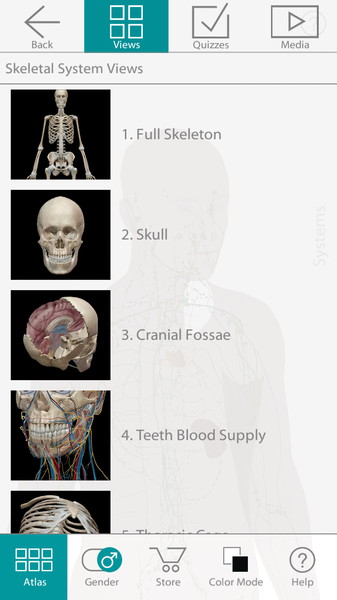

Трехмерный атлас по анатомии рассматривает модели мужской и женской анатомии. Для этого достаточно будет выбрать F или M. Далее воспользуйтесь удобным поиском по системам (Select System) и Вы сможете рассмотреть любое сочетание анатомических образований на черном или белом фоне, прочитать и услышать их полное описание (положение, форму, функциональные и физиологические особенности). Приложение само по себе очень чувствительно. Удивительно то, что при максимальном увеличении изображение не теряет своей детализации. Пользователь в полной мере сможет воспользоваться жестами многозадачности и понимание строения человека будет максимально эффективным.

- Каждая модель содержит порядка 4600 анатомических образований.

- Есть функция предпросмотра, которая включает в себя сотни миниатюрных изображений.

- Модель можно вращать, наклонять, приближать – одним словом, изучать под любым углом.

- Встроенный поиск анатомических образований по их названию.